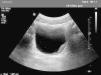

Varón de 11 años de edad, natural de Mali, residente en España 3 meses, que fue remitido al hospital para estudio de hematuria macroscópica terminal intermitente de un año de evolución. Ha presentado además 2 infecciones urinarias. La exploración física fue normal, salvo lesiones residuales de picaduras de insectos en las extremidades. Aportó una analítica completa, destacando una eosinofilia del 34%. Serologías de lúes, virus de la inmunodeficiencia humana, virus de la hepatitis B y parásitos en heces: negativo. Sedimento urinario con 50-100 hematíes/campo. Ante la sospecha de afección vesical por esquistosomiasis, se solicitó una ecografía renal, que demostró la presencia de engrosamientos nodulares vesicales compatibles con esquistosomiasis vesical (fig. 1) y se detectaron huevos de esquistosomas en una de las 3 muestras de orina recogidas (fig. 2). Recibió tratamiento con praziquantel: 2 dosis de 40mg/kg a las 0 y 4 semanas, desapareciendo la clínica tras la primera dosis. A los 3 meses, muestras de orinas negativas. Normalización ecográfica al año.

El diagnóstico se establece tras la visualización en fresco de los huevos en el sedimento urinario. Pueden no observarse en las fases iniciales de la infección o si el grado de infestación es bajo. Las muestras deben de ser recogidas varios días por la mañana, cuando se produce una máxima eliminación de los huevos por orina9. Las pruebas serológicas no distinguen entre infección antigua o reciente. Las pruebas de imagen establecen la severidad, las complicaciones y las secuelas de la infección. La ecografía abdominal demuestra las lesiones granulomatosas en la pared vesical, así como otras lesiones y complicaciones como la uropatía obstructiva. La cistoscopia permite la visualización directa de las lesiones, así como la toma de biopsias de la pared vesical donde se demuestran los granulomas y los huevos8.